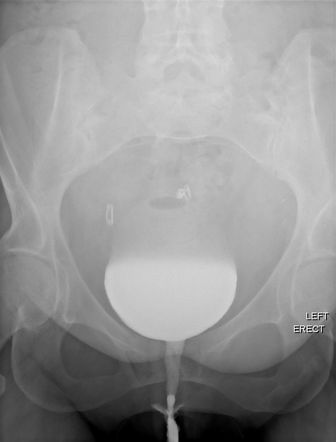

Voiding cystourethrogram is a diagnostic procedure which aims at providing x-ray images of the bladder while it is voiding (Fig. 26). It is conducted through inserting contrast medium into the bladder so urinary reflux and urethral strictures can be recognized easily.